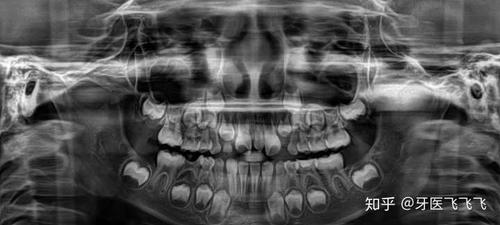

小孩牙齿x光图,小孩牙齿图片恒牙图片

看牙齿的x光片如何看出牙齿是恒牙还是乳牙?

小孩牙齿图片恒牙图片

小孩牙齿x光

没换牙的小孩的x光图

正常儿童牙齿x光图

儿童换牙x光图